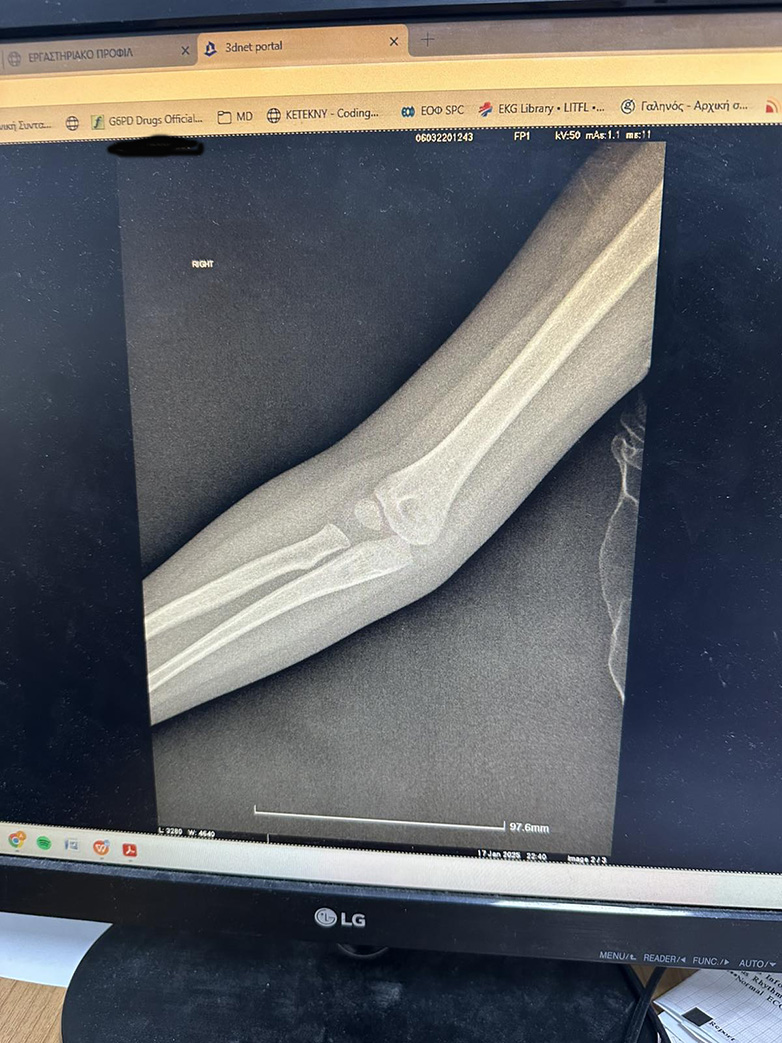

Στη συνέχεια ο πατέρας του παιδιού, μιλώντας με τον νεαρό γιατρό -που μάλλον ήταν ειδικευόμενος- όπως μας είπε, ρώτησε τι θα γίνει με το παιδί το οποίο εξακολουθούσε και πονούσε πολύ. Ο γιατρός τους έστειλε να βγάλουν ακτινογραφίες. Όντως έβγαλαν ακτινογραφίες της μικρής και στη συνέχεια ο γιατρός τις πήρε μέσω φωτογραφίας στον υπολογιστή του, αλλά επειδή ο ίδιος δεν ήταν ορθοπεδικός δεν μπορούσε να κάνει διάγνωση.

Ο πατέρας της μικρής τον ρώτησε αν έχει επιστρέψει ο ορθοπεδικός στο πόστο του λαμβάνοντας αρνητική απάντηση. Στη συνέχεια ρώτησε αν θα επιστρέψει ο γιατρός, χωρίς αυτή τη φορά να λάβει κάποια καταφατική απάντηση από τον γιατρό, που συνομιλούσε μαζί του. Αντ’αυτού, ο γιατρός είπε ότι θα στείλει τις ακτινογραφίες στο Viber στον εφημερεύοντα ορθοπεδικό, ώστε να τις δει και να του δώσει οδηγίες!

Οι ακτινογραφίες στάλθηκαν στο Viber του εφημερεύοντα ορθοπεδικού, ο οποίος μπορεί να μην ήταν στη εφημερία του στο νοσοκομείο -ως όφειλε- ήταν όμως…online. Ο εφημερεύων – και απών – ορθοπεδικός απάντησε αμέσως, όταν έλαβε τις φωτογραφίες με τις ακτινογραφίες – οι οποίες είναι αυτές που βλέπετε – και έκανε ή μάλλον καλύτερα δεν έκανε διάγνωση, απαντώντας πάντα μέσω Viber ότι δεν μπορεί από το κινητό να διακρίνει αν υπάρχει ή όχι σοβαρό πρόβλημα. Μάλιστα, συνέχισε λέγοντας ότι καλύτερα θα ήταν να φύγουν οι γονείς με το τριών ετών παιδί τους και να πάνε στην Πάτρα στο νοσοκομείο Παίδων «Καραμανδάνειο».